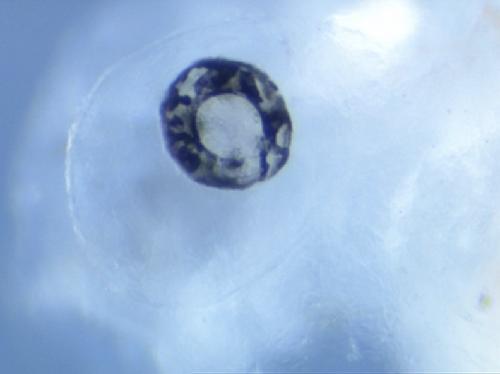

A mutation affecting retinal epithelium identified in the Mill Hill screen for ENU-induced mutations. Splicing mutation in the atp7a copper transporter which results in the deletion of the C-terminal 125 amino acids.Model for Menkes disease. |

Retinal epithelium pigmentation is variegated, melanocytes reduced, head cartilage defects. |

Xtr.atp7a mutant embryos (also known as kaleidoscope /kal) show variegated retinal pigmentation, decreased melanophore number, and head cartilage defects